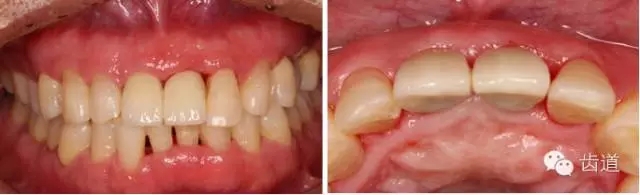

戴牙(基臺(tái)就位)

戴牙

治療前后對(duì)比

戴牙一年前后對(duì)比